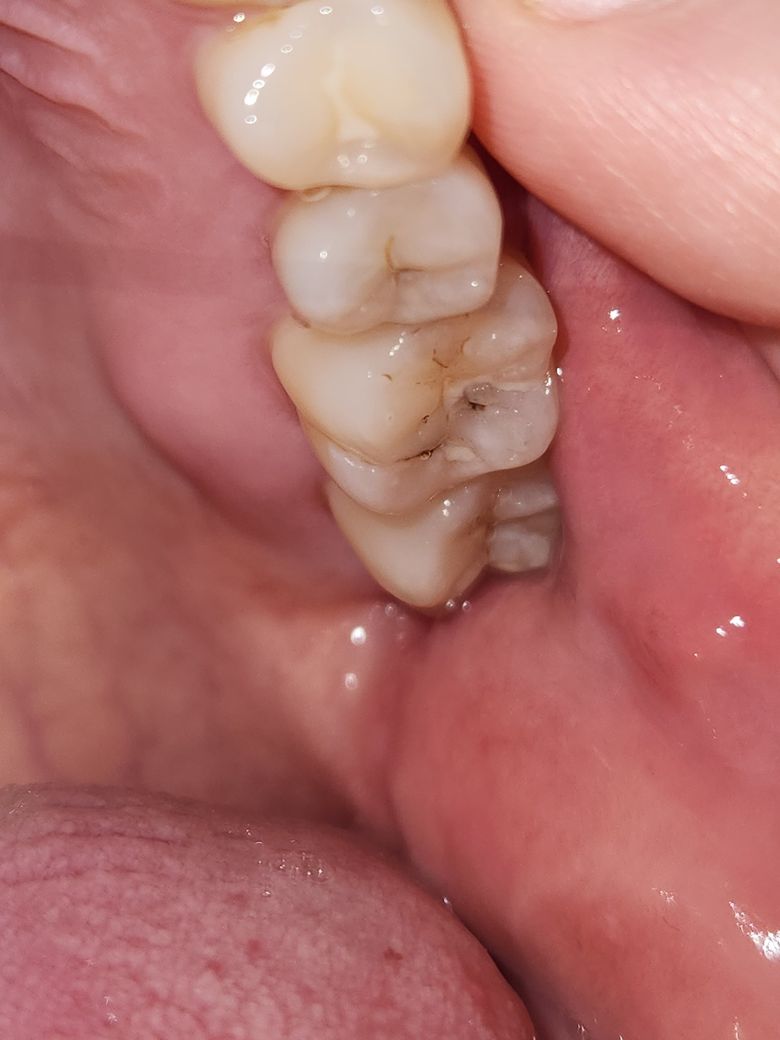

25번 소구치 신경치료 해야할까요?

25번 소구치를 인접면충치가 있다고 신경치료 하자고합니다.

지금 흔들리거나, 통증도 전혀 없고 시린 증상도 없는데..

갑자기 멀쩡한 이빨 신경 죽이고 크라운 씌우라고 하니

당황스럽습니다.. 과잉진료가 아닌가 의심스럽기도합니다

선생님들 육안으로 보기에 어떠신지 의견좀 남겨주세요

엑스레이 사진은 따로 못찍었습니다ㅠ

사진으로만의 충치의 범위를 정확하게 알기 힘듭니다. 자세한 확인을 위해서는 엑스레이 사진이 필요할 수 있습니다. 충치가 신경까지 있어도 신경이 죽었다면 통증이 느껴지지 않은 경우도 있으니 치과에서 진료를 받아보세요.

인접면 우식은 육안으로는 확인이 어렵습니다. 엑스레이 사진을 구해오시면 도움을 드릴 수 있습니다.

육안상으로는 신경치료를 판단하기 어렵습니다. 엑스레이 사진을 찍어서 충치가 어느정도 진행됫는지 보고 판단을 할것같습니다.